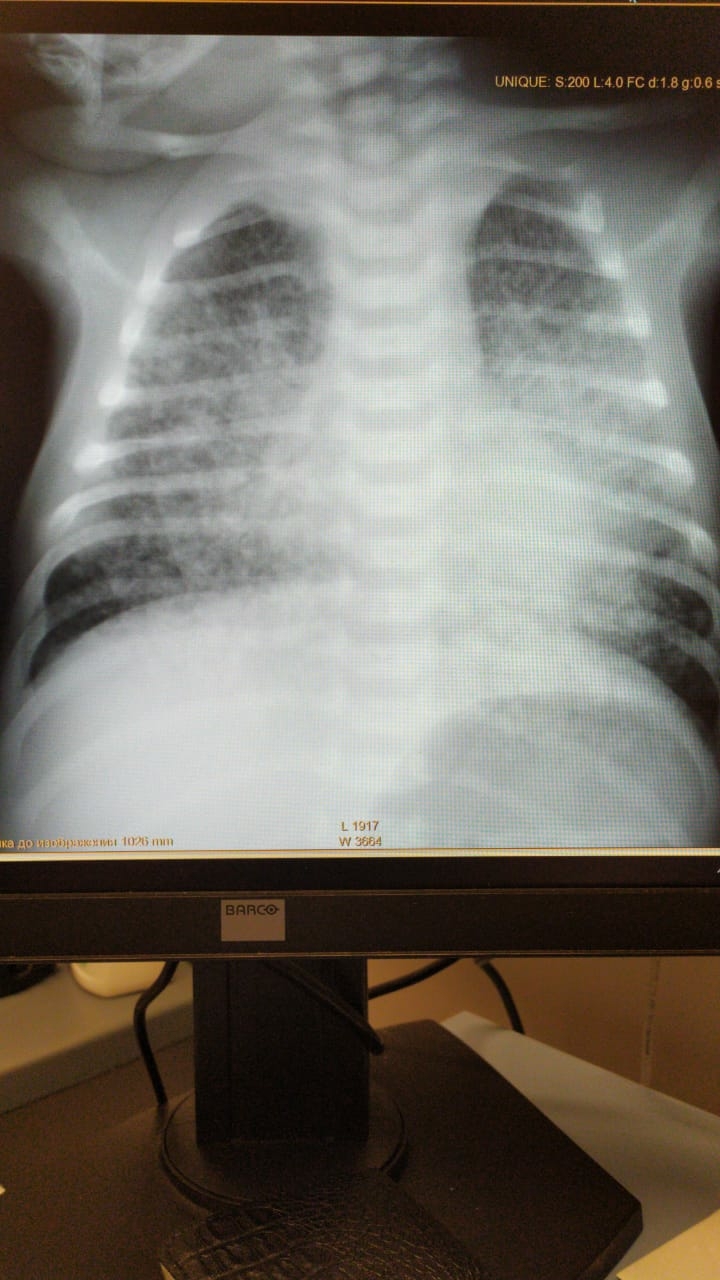

Так выглядит вирусная пневмония на рентгене. Дыхательная недостаточность - причина 99 процентов легальных исходов. Главный вопрос что делать?